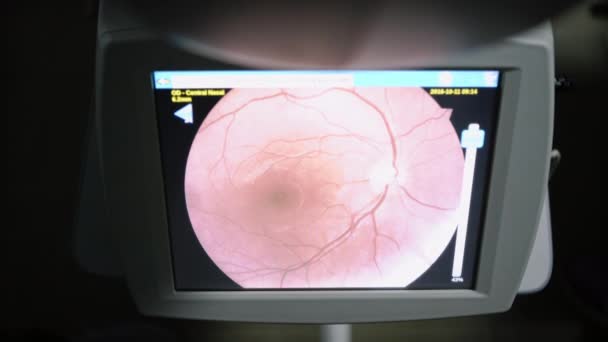

Eye Test Computer Image Of Retina Showing Optic Disc Cupping